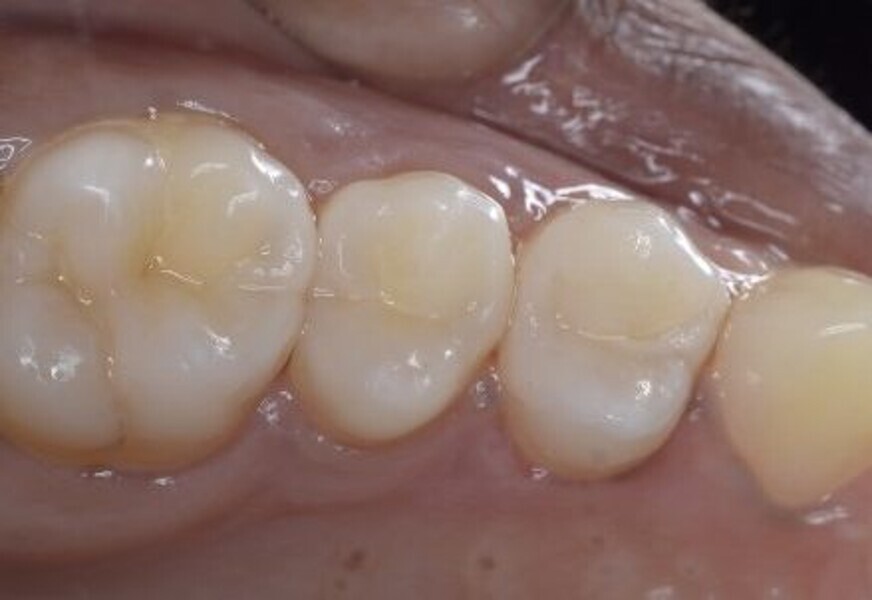

Predictable posterior restorations